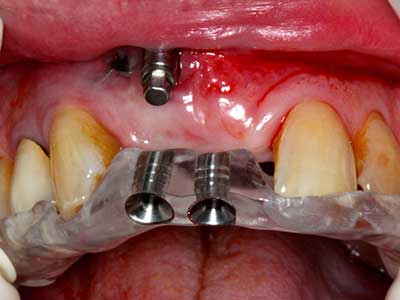

Die Präparation des lateralen Fensters bei der externen Sinusbodenelevation stellt gerade für chirurgisch unerfahrene Implantologen eine große Herausforderung dar. Die knöcherne Bedeckung der Kieferhöhle ohne eine Verletzung der darunterliegenden Schneider’schen Membran abzutragen ist dabei nur ein Teil der Operation – nach Schaffung eines ausreichenden Zugangs muss die Kieferhöhlenschleimhaut vorsichtig mobilisiert werden, um Raum für das einzubringende Material bzw. die Implantate zu schaffen. In dieser Indikation ist die Piezochirurgie zweierlei hilfreich: zum einen kann durch Verwendung diamantierter Instrumente eine selektive Knochenabtragung erfolgen und die darunter liegende Schleimhaut bleibt bei vorsichtiger Vorgehensweise intakt. Zum anderen unterstützen die Ultraschallfrequenzen zusätzlich eine komplikationslose Ablösung der Schleimhaut – sie werden durch spezielle stumpfe Ansätze in den Spaltraum zwischen Schleimhaut und Kieferhöhlenboden übertragen (Cassetta, Ricci et al. 2012, Pereira, Gealh et al. 2014) (Rickert, Vissink et al. 2013). So erscheint es nicht verwunderlich, dass in aktuellen Übersichtsarbeiten über die externe Sinusbodenelevation neben der Verwendung von rauen Implantatoberflächen und dem Einsatz von Knochenersatzmaterialien auch der Einsatz von piezoelektronischen Geräten als positiv bewertet wird (Wallace, Tarnow et al. 2012).

Wie sich in der Vergangenheit gezeigt hat stellt prinzipiell jeder knochenchirurgische Eingriff eine mögliche Indikation für die Piezochirurgie dar. So lässt sich die Präparation des mobilen Segmentes bei der Distraktionsosteogenese (Abb. 23-25) und der Sandwichosteotomie mit speziellen Ansätzen bewerkstelligen, ohne die für den Erfolg beider Techniken essenzielle Blutversorgung des krestalen Anteils zu gefährden (Gonzalez-Garcia, Diniz-Freitas et al. 2008).

Für die Entnahme von Implantaten ist die Präparation eines vestibulären Knochendeckels möglich, der nach Entfernung der Implantatschraube refixiert wird und auf diesem Wege die Kontur des Alveolarfortsatzes erhält.